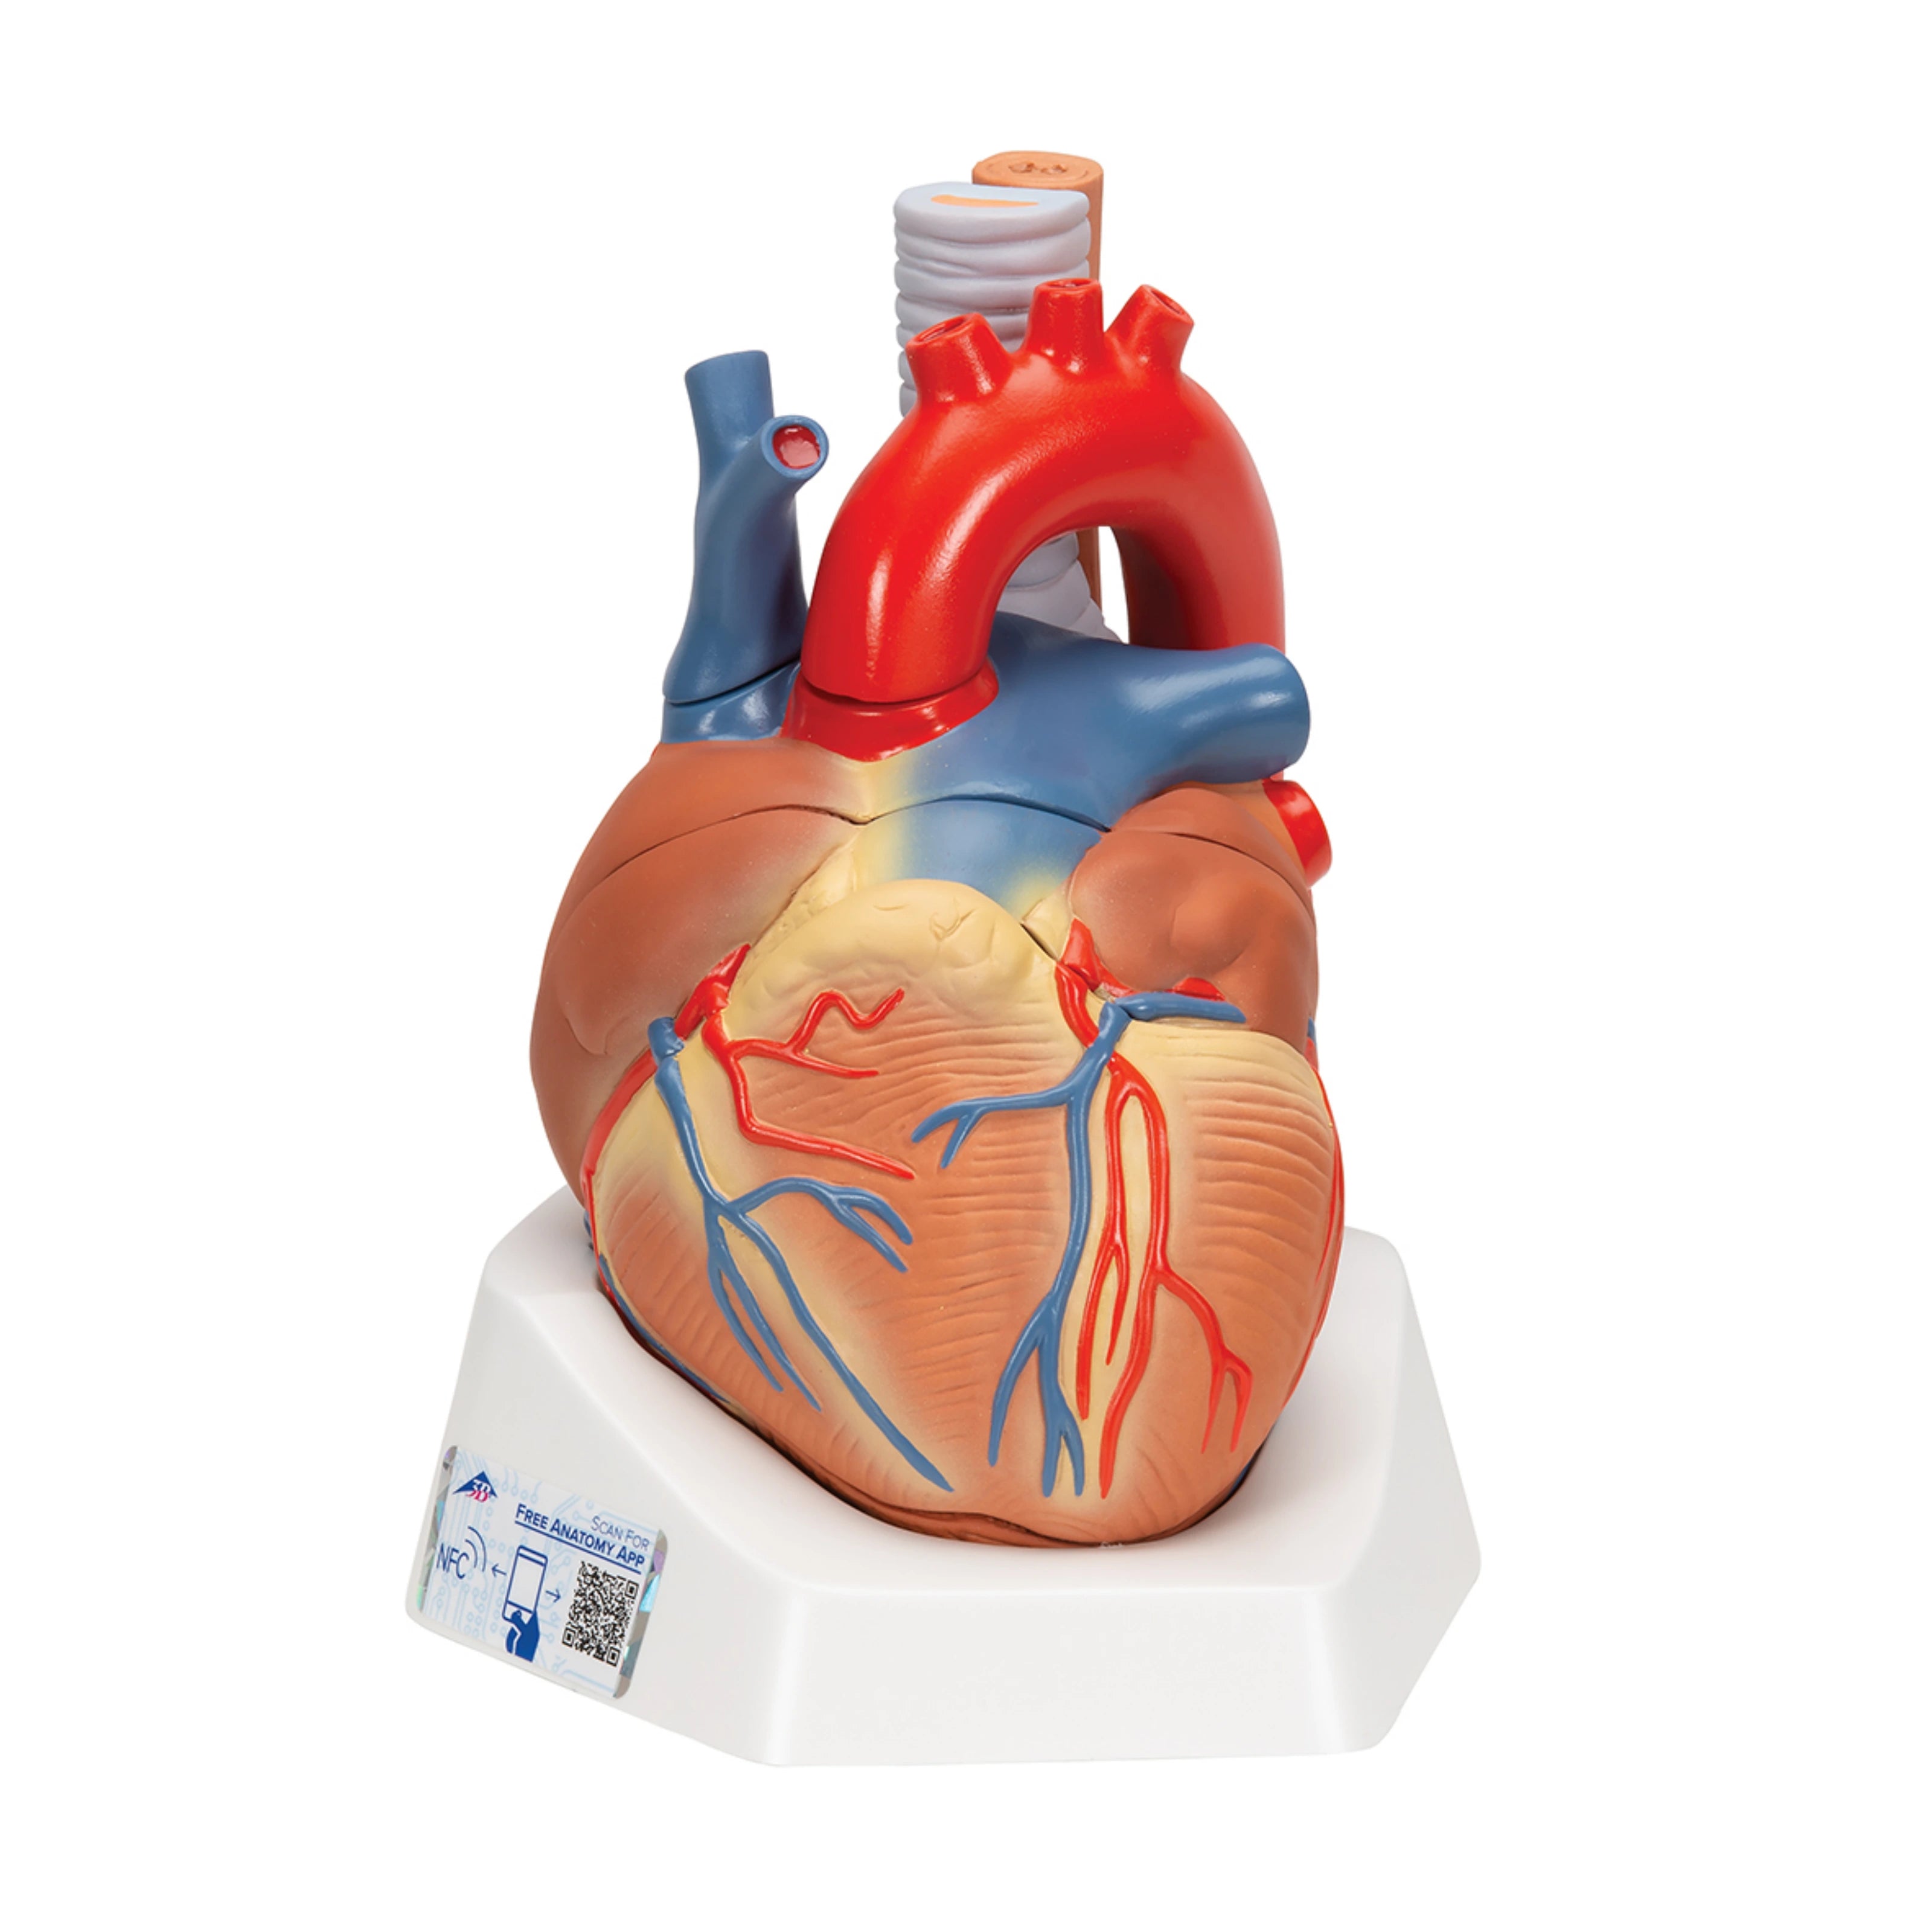

Órganos internos: corazón, pulmones, hígado, riñones, sistema digestivo y reproductivo.

Modelos especializados: cardiología, neurología, ginecología, ortopedia y más.